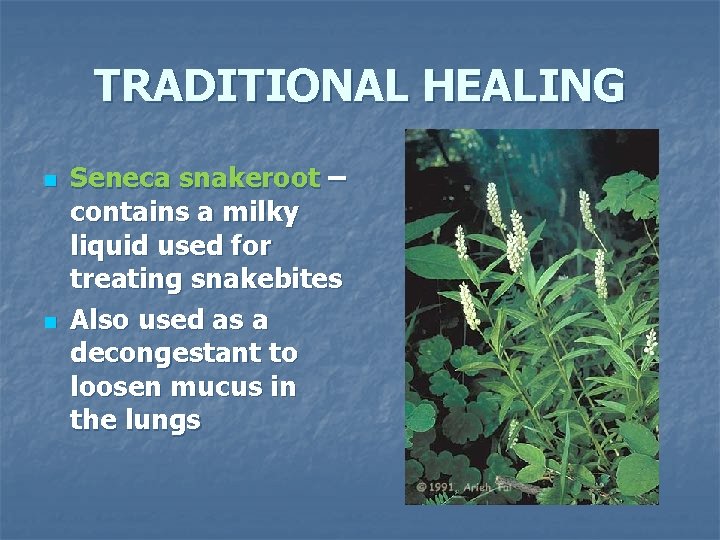

TRADITIONAL HEALING n n Seneca snakeroot – contains a milky liquid used for treating snakebites Also used as a decongestant to loosen mucus in the lungs